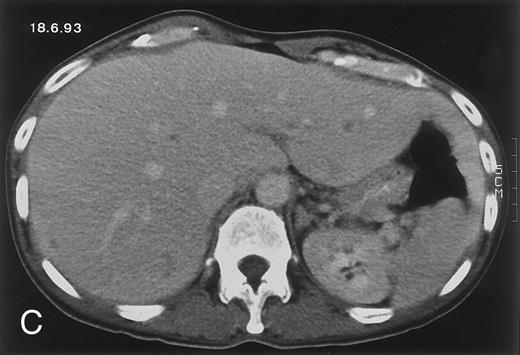

Radiologic evolution in patient B. (A) Postcontrast abdominal CT scan on February 10, 1994 shows multiple small hypodense areas in all segments of the liver suggestive of hepatic candidiasis. Twenty-four days previously, the patient had recovered from severe neutropenia after the second cycle of chemotherapy for ALL. (B) On May 4, 16 days after the neutrophil count had dropped below 500/μL in the third chemotherapy cycle, there is clear improvement of the radiologic findings, with only a few hypodense areas in the liver.